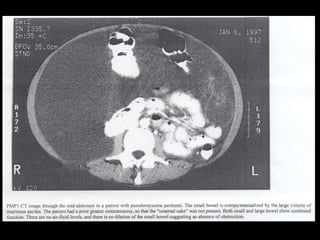

Pseudomyxoma peritonei (PMP) is a rare condition characterized by gelatinous ascites resulting from the rupture of appendiceal mucinous tumors, leading to significant abdominal complications. The incidence is approximately 2 cases per million per year, with a predominance in females, and diagnosis often relies on imaging techniques like ultrasound and CT scans. Effective treatment involves cytoreductive surgery combined with hyperthermic intraperitoneal chemotherapy (HIPEC) to manage disease progression and improve outcomes.